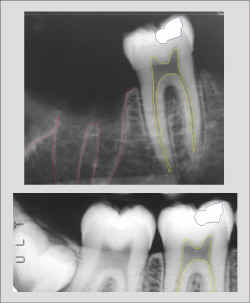

Identificação Humana por Comparação Computadorizada de Imagens

Radiográficas Dentárias